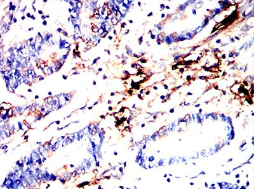

IHC    1/200 - 1/1000